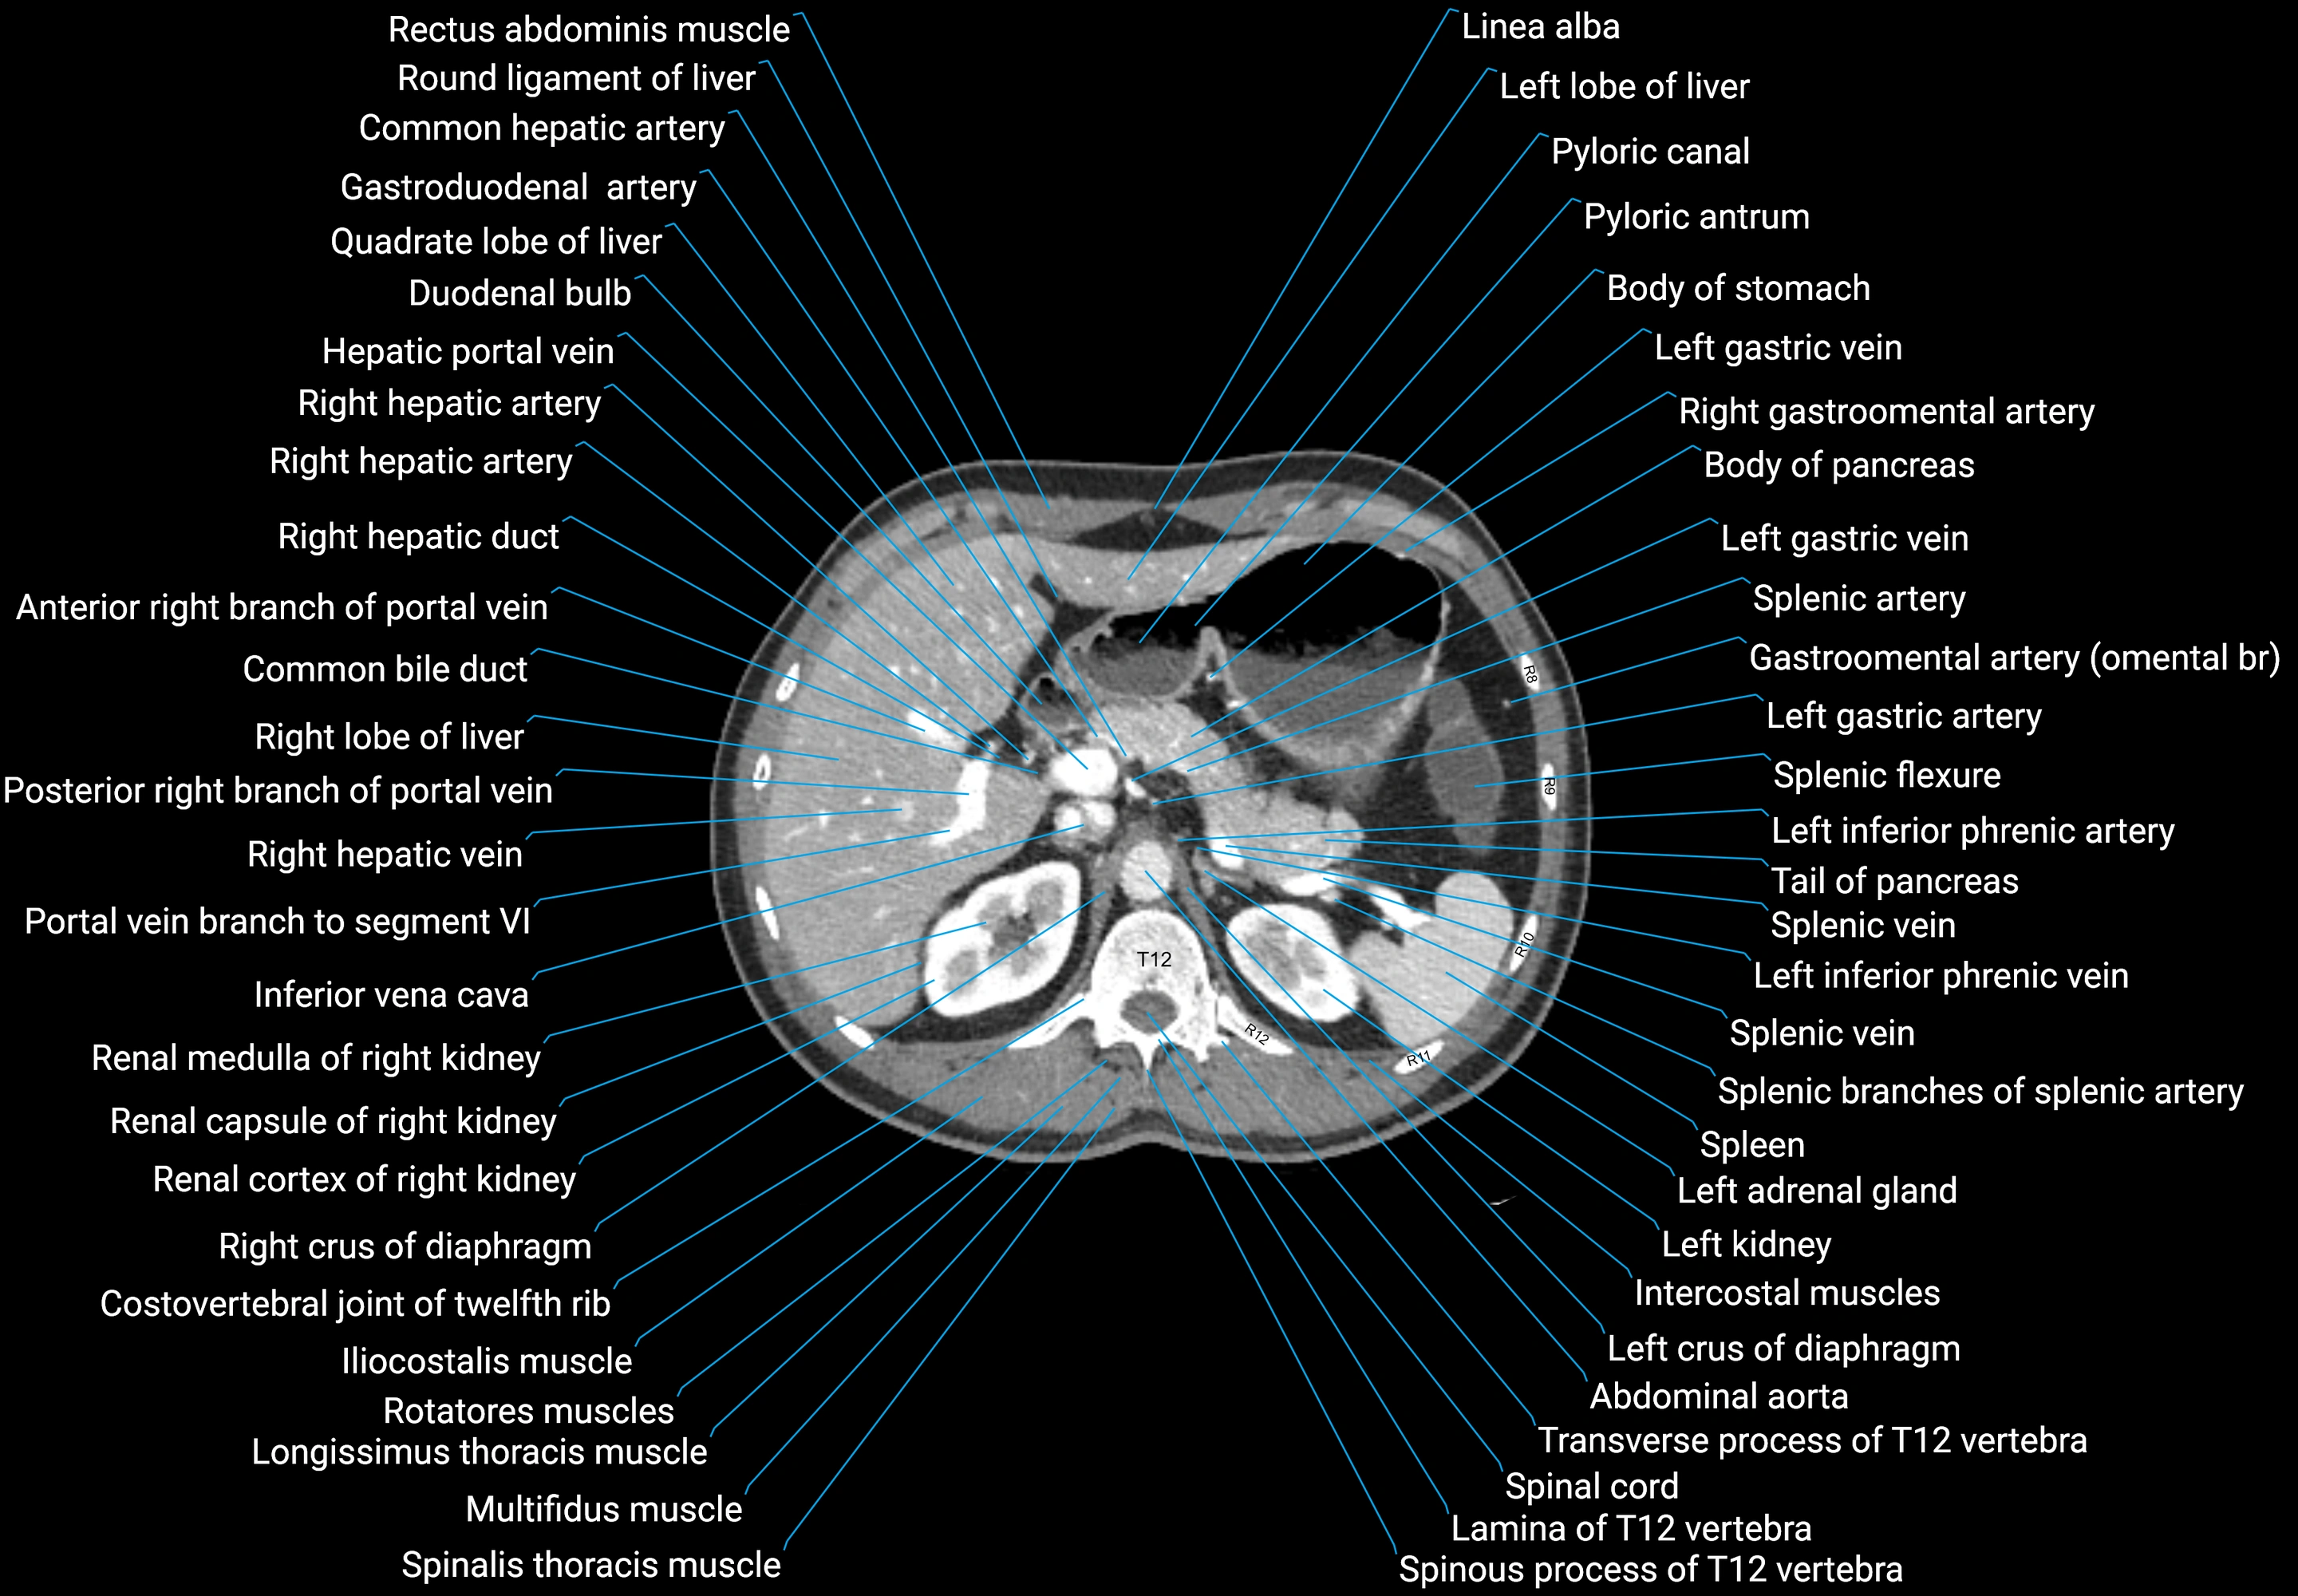

CT images